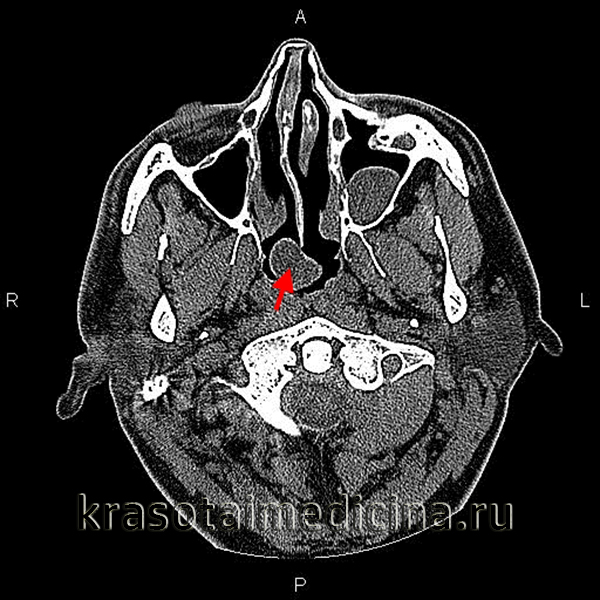

Больной был госпитализирован в отделение оториноларингологии РГБ ЛПУ «Карачаево-Черкесская республиканская клиническая больница», где при видеофиброэндоскопическом исследовании в задне-верхнем отделе носоглотки справа было обнаружено округлое, плотное образование размерами 2,0×2,0 см, с четкими контурами и выраженной инъекцией сосудов (рис. 1).

Рис. 1. Больной А., 27 лет. Эндоскопия носоглотки. Fig. 1. PatientA., aged 27 years. Endoscopic examination of the nasopharynx.Определяется округлое, плотное образование справа, рядом с глоточным устьем слуховой трубы. The rounded dense tissue mass is visible on the right side in the vicinity of the pharyngeal opening of the Eustachian tube.

Слизистая оболочка в области глоточного отверстия слуховой трубы справа несколько гиперемирована, на задней стенке носоглотки — слизисто-гнойное отделяемое. Носовое дыхание затруднено.